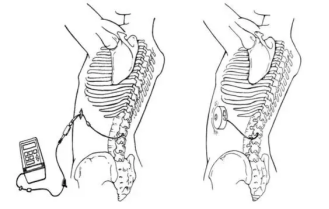

鞘内吗啡镇痛泵植入术(一)

鞘内吗啡镇痛泵植入术,又称“植入式鞘内药物输注系统”,是一种先进的微创介入镇痛技术。它通过将药物直接输送到脊髓周围的脑脊液中,像建立一个“直达疼痛中枢的精准给药通道”,从而高效地控制顽固性疼痛。它真正实现了 “用最小的药量,达到最强的效果,产生最少的副作用”的精准医疗目标,为众多深受顽固性疼痛折磨的患者提供了重返高质量生活的希望,是“舒适化医疗”理念的杰出体现。是目前国际上治疗顽固性疼痛及癌痛的核心技术。

鞘内吗啡本治疗示意图